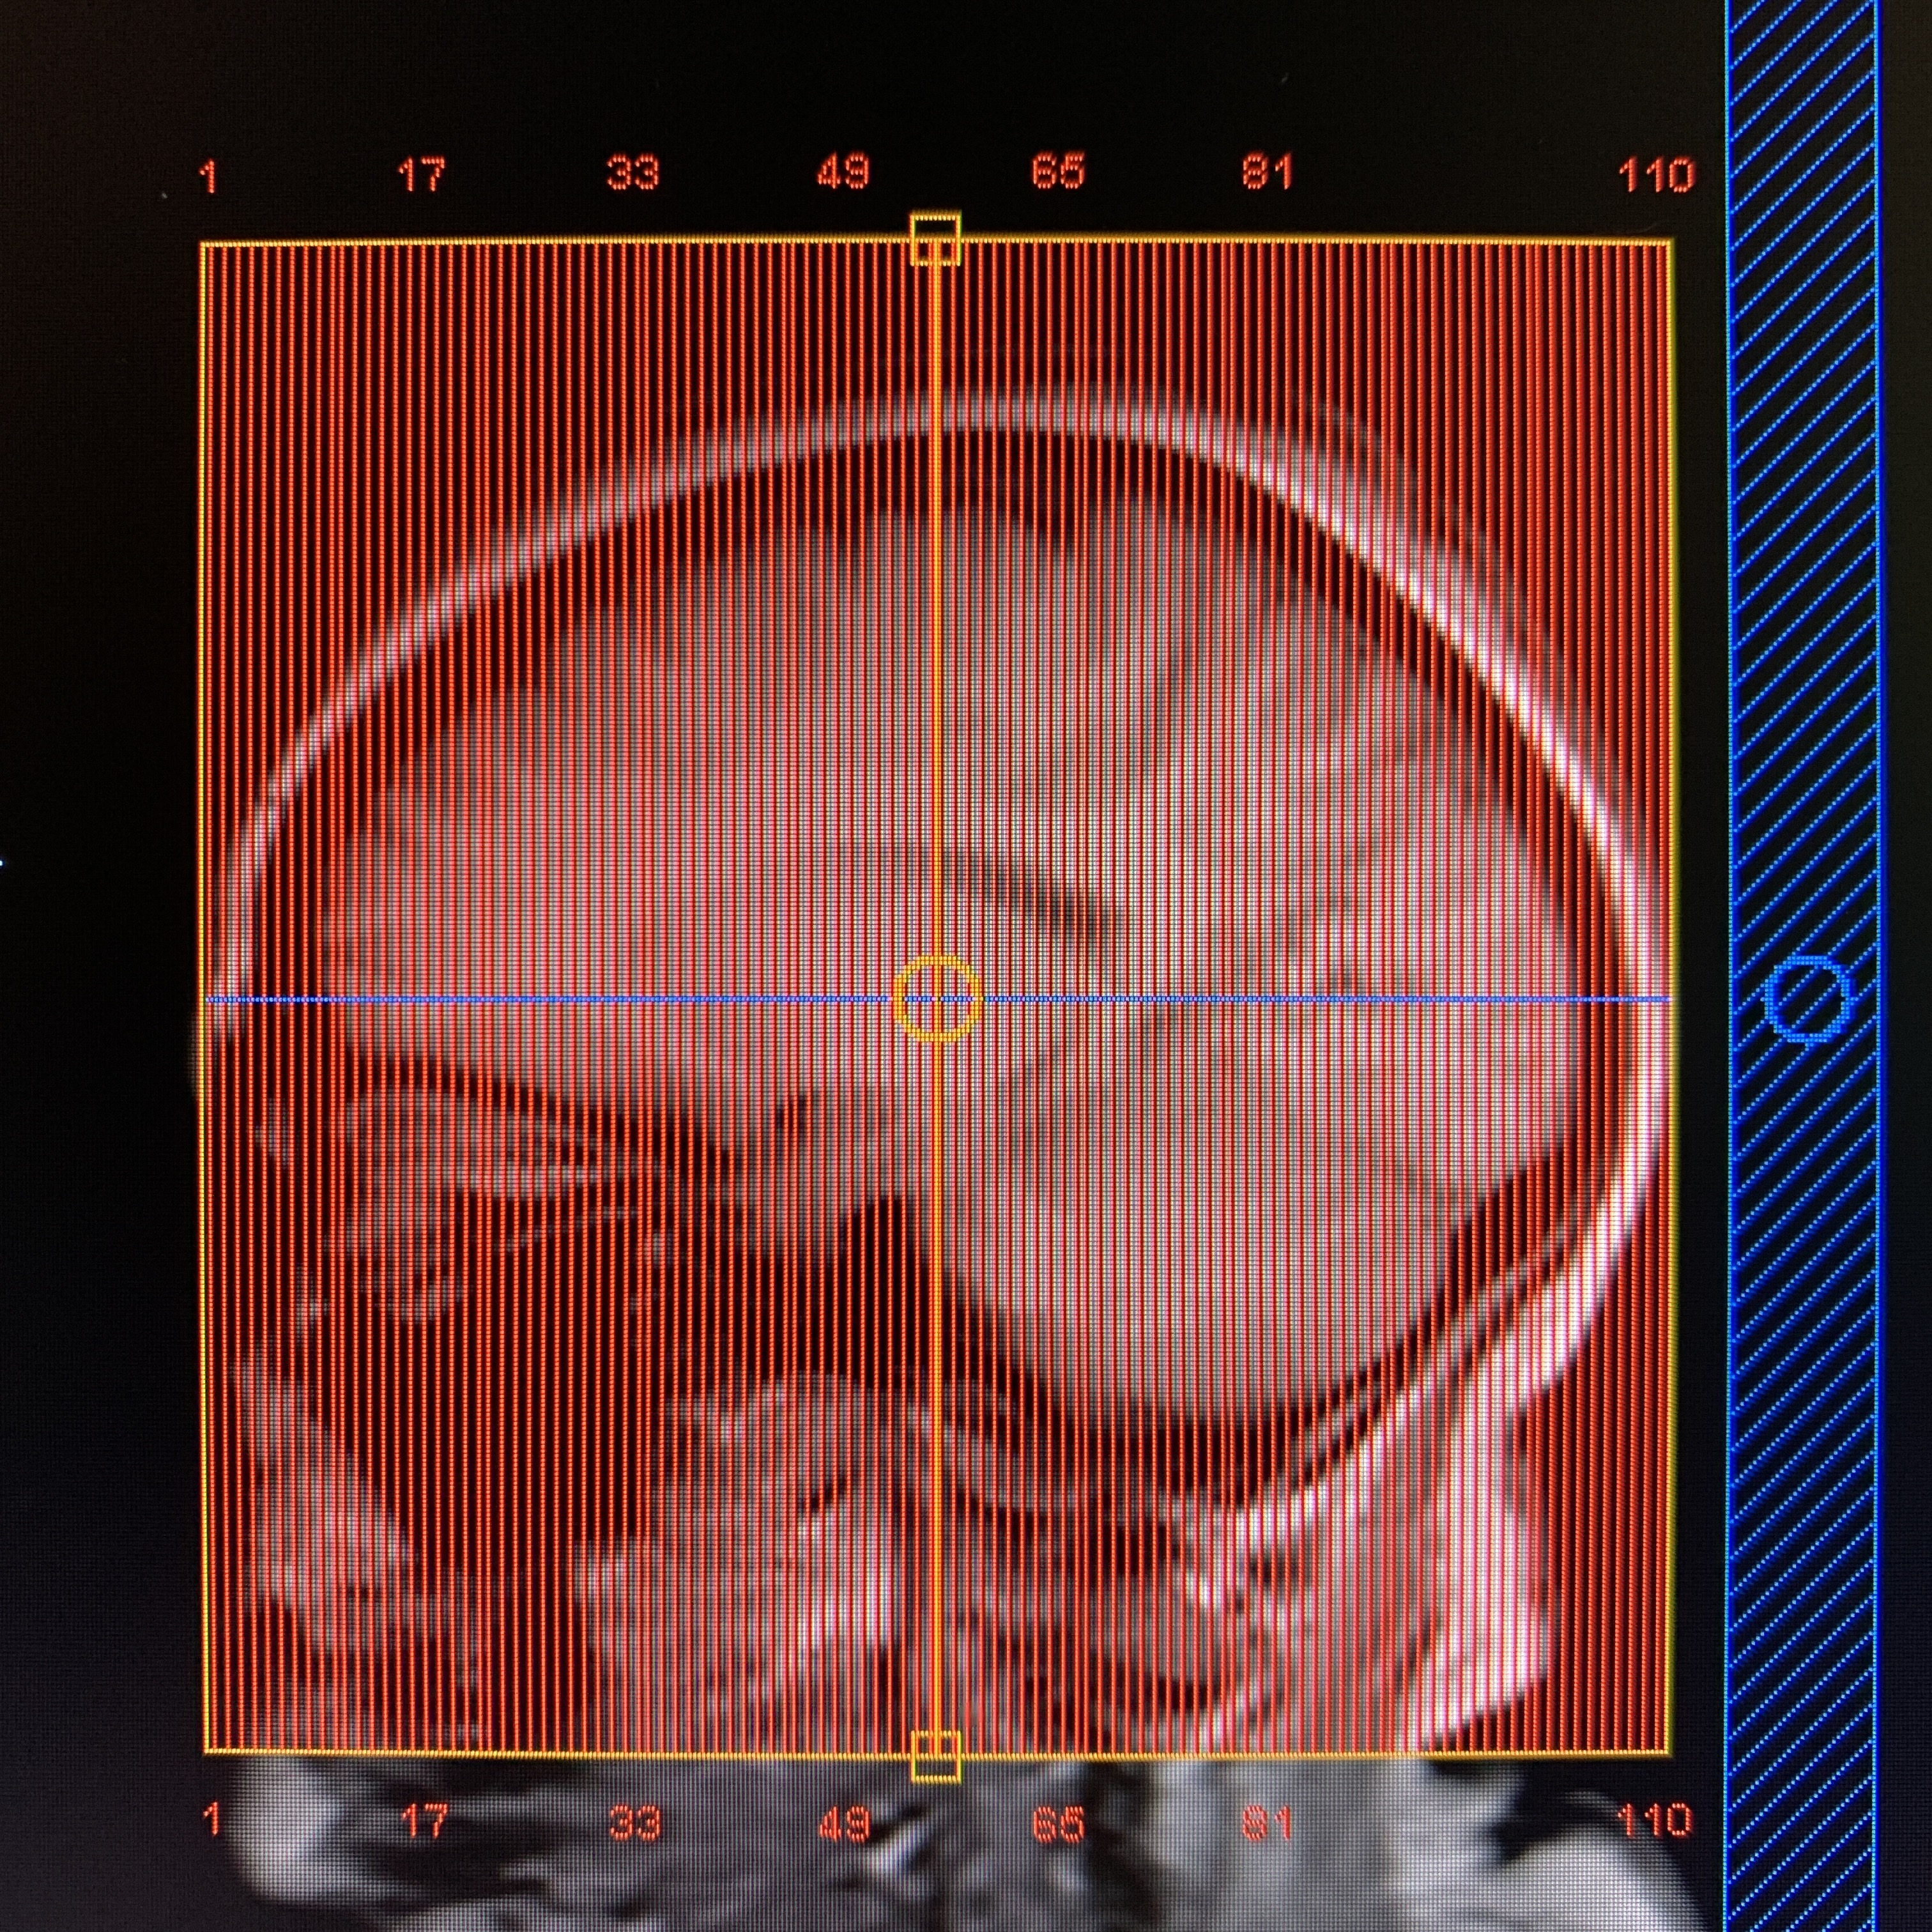

Always acquired in both axial and coronal planes.

“M2D”= Multiple 2D. Multiple single slice acquisition. A number of slices are scanned in sequential order.

| AXIAL | T1 | M2D FFE | 2mm | -0.5mm | None | 23cm | Whole head,vertex to skull base |

| COR | T1 | M2D FFE | 2mm | -0.5mm | None | 23cm | Frontal through occipital, skin to skin |